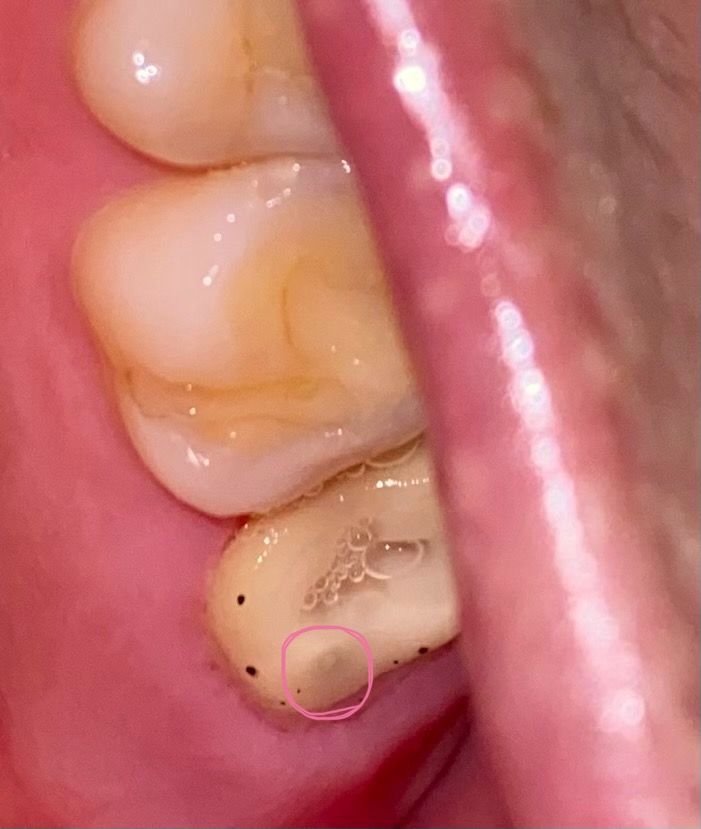

1) 선으로 표시해둔 검은 반점이 궁금합니다

검은반점이 있고 가운데는 흰색으로 동그랗게 있네요

2) 검은색 바닐라빈마냥 콕콕 박힌 것들은 무엇인가요?

피딱지인가 싶었는데 면봉으로 닦이지 않습니다

• 2번 째 사진

검은 점들은 교합을 체크할 때 쓰는 교합지로 보이며 내부 검은색은 치아 내부가 그냥 비치는 것 같습니다.

동그라미 친곳은 치아색이 저렇게 보이는거같습니다. 문제가 잇는건 아니니 걱정하지않으셔도 되고 두번쨰 사진에 보이는 까만색 점은 교합지로 체크를 하면서 생긴 점인거 같습니다.

검은색으로 바뀐 점은 레이저로 인해서 다듬어진 연조직일 수 있습니다 이런 것들은 대부분 시간이 지나면서 없었지만 사진에 보이는 치아의 어두운 부분은 치아에 한 부분이기 때문에 크게 걱정하지 않으셔도 될 것으로 보입니다